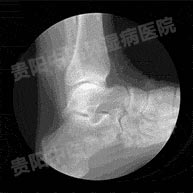

双手双足痛风石怎么治疗?2016-12-01